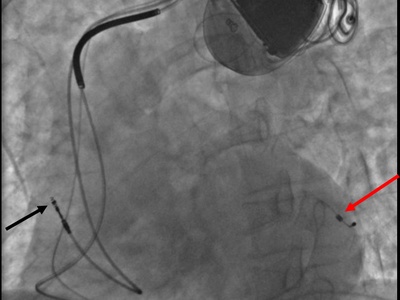

Pacemaker/ICD Implantation

Implanting a device under the skin with leads to the heart to regulate heart rhythm or deliver shocks for dangerous arrhythmias.